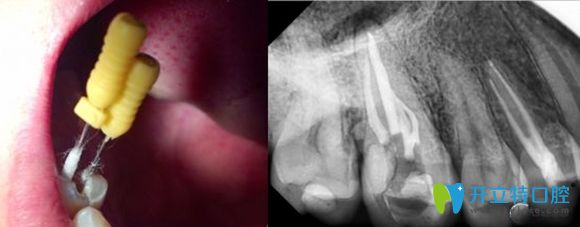

根管治疗就是牙医利用专用的器械,去除牙齿内部感染的牙髓以及感染的牙本质,还有毒性分解产物,并进行适当的消毒,然后再进行严密充填根管,防止发生根尖周病变,或者是促进根尖周病变愈合的一种治疗方法。

常规根管治疗不需要显微镜,根管较疑难的时候会用,现在有些医生建议所有根管在查找根管和扩挫都用显微镜,这个必须要有操作基础。

并且后牙根管数目多且形态复杂,治疗的难度更大,因此后牙根管治疗术费时且繁琐,费用相对较高些,再加上牙冠的话,也就是5000元左右了。